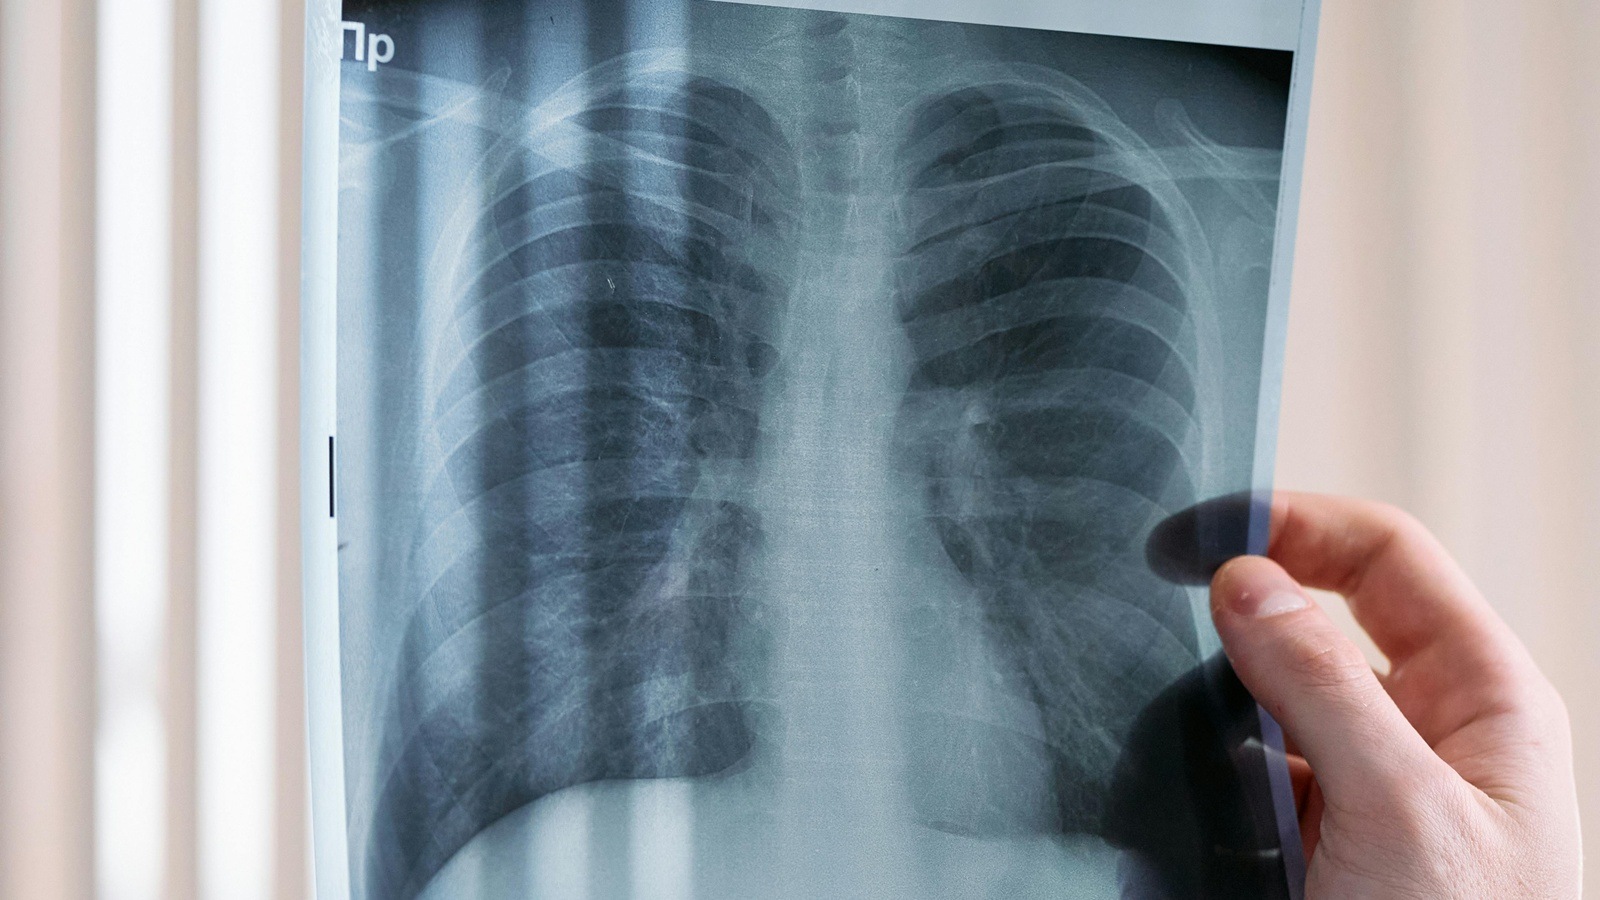

Lung scanA biopsy confirmed stage 2 lung cancer, a treatable window. (Source: Pixels)

A 31-year-old woman from Ghaziabad, who had never smoked in her life, first coughed up blood, which subsided with some drugs that her neighbourhood doctor had prescribed. But then she felt a left-sided chest pain. Fearing a lung infection, she walked into the clinic of Dr Arvind Kumar, chairman, Lung Transplant, Chest Surgery/Oncosurgery, at Medanta, Gurugram, because she worked at an office nearby. “An X-ray showed a mass in the upper part of her left lung. A biopsy confirmed stage 2 lung cancer, a treatable window. She is disease-free and has returned to work but her case shows a disturbing trend,” he says.